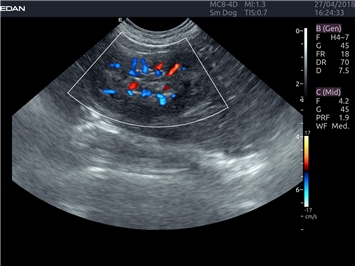

EDAN Acclarix LX4 VET представляет собой профессиональную ультразвуковую систему, специально разработанную для ветеринарных исследований. Сочетание стабильности, высокой производительности и эффективности делает эту систему идеальным выбором для современной ветеринарной практики.

Трехмерная реконструкция ЦДК:

Да

Энергетический допплер: